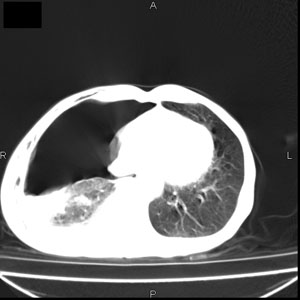

患者男,77岁,于3日前从树上摔下,头部查ct示蛛血,硬膜下出血,上腹部ct未见明显异常,右侧胸腔积液,左侧如常。肺部拍片示右侧肋骨多发骨折住院后今日来查肺部ct,我看到的是1。右侧胸腔血气胸并右肺上叶,中叶压缩性肺不张,2。右肺下叶肺挫伤并多发肋骨骨折,肌内及皮下积气3。左侧少量胸腔积液,我想请教的是3天前左侧胸腔里没有积液今天怎么出现了呢,是什么原因呢?请讨论。